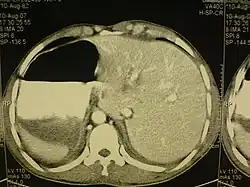

El situs inversus es una extraña anomalía congénita que puede afectar a varios órganos y tiene un carácter genético. Consiste en una alteración en la alineación de los órganos dentro del cuerpo, por la que estos se encuentran en el lado opuesto (imagen de espejo).